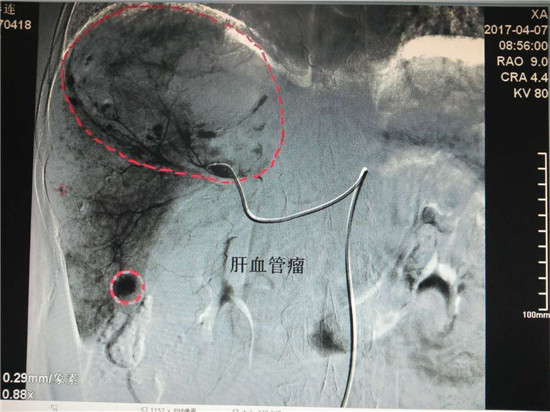

患者孙某,女性,62岁,在我院体检时发现患有巨大肝血管瘤(130mm×88mm),4月7日,在渭南市中心医院介入科行介入微创手术治疗。术前,科主任李建国详细分析评估了病情,组织科室人员制定了严密的手术方案,术中精细操作,在全体医护人员的密切配合下,历时40分钟,成功对患者肝脏巨大血管瘤实施了肝动脉超选择介入栓塞术。治疗过程患者处于清醒状态,无痛苦,术毕生命体征正常,安返病房。